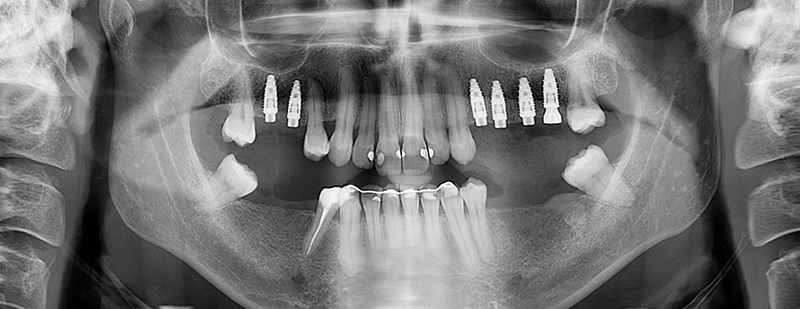

Fig. 25 : résultat après la chirurgie guidée.